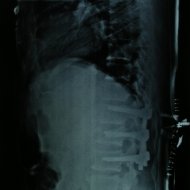

Omurga Kırığı

Omurga kırıkları osteoporozun olmadığı sağlıklı kişilerde trafik kazası ya da yüksekten düşme gibi yüksek enerjili travmalar sonucu oluşur. Eğer omurilik basısına neden olursa kısmi ya da tam felç ile sonuçlanabilir.

Eğer travma ilerleyen dönemde deformiteye yol açmayacaksa veya sinirlere baskı yaparak nörolojik bulguya neden olmadıysa korse ile tedavi edilebilir. Bu amaçla sert polietilen korseler ya da metalden yapılmış çerçeve tipi korseler kullanılabilir. Omurganın ağır zarar gördüğü durumlarda ileride oluşabilecek deformiteyi engellemek için omurganın vida ve çubuklarla sabitlenmesi gerekebilir. Nörolojik bulgu oluşturan bir kemiksel bası varsa, aynı seansta bu bası da ortadan kaldırılabilir.